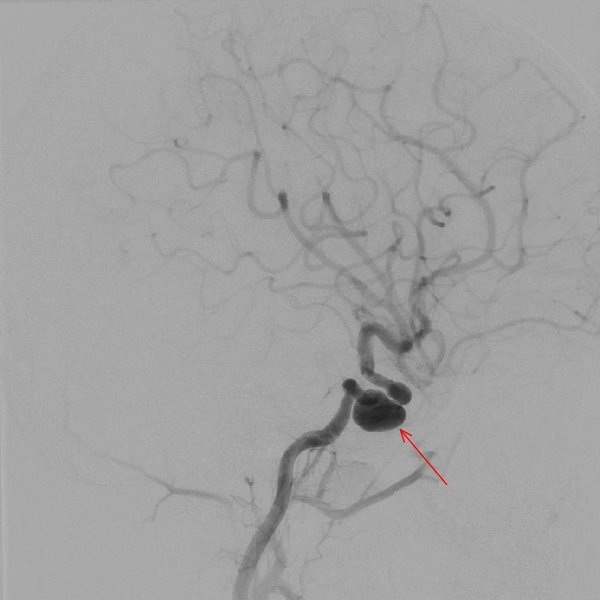

Die untenstehenden Bilder zeigen einen kleinen Patienten mit einem Aneurysma der inneren Halsschlagader. Das linke Angiogramm zeigt das 1,3 Zentimeter große Aneurysma. Das rechte Angiogramm zeigt die Kontrolluntersuchung nach Ausschaltung der Gefäßaussackung (Pfeilmarkierung) und somit wieder ein physiologisches Bild der hirnversorgenden Gefäße.